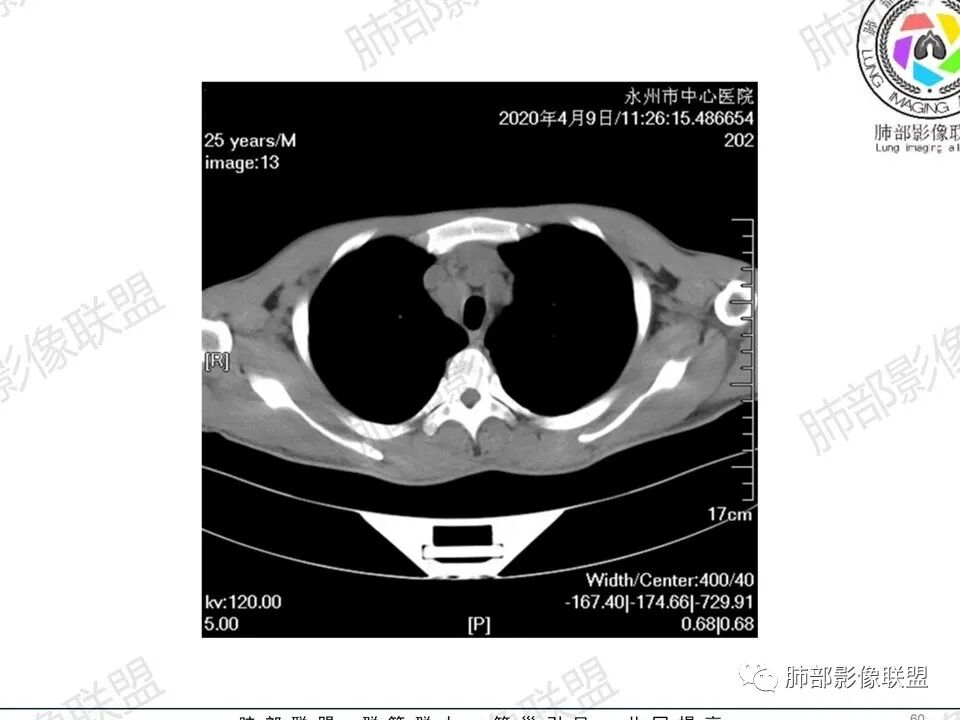

1、临床信息:青年男性,慢性病程,咳嗽气促,伴盗汗胸痛。

2、实验室检查:低色素性贫血,血沉快,铁蛋白明显增高,凝血功能降低,蛋白降低,乙肝表面抗原阳性,叶酸低,CRP 高,白细胞及中性高。

3、影像表现:双肺散在斑片影及结节影,部分结节内可见血管穿行,斑片影沿支气管血管束分布,近胸膜侧病变收缩不明显。部分中央淋巴间质增厚,小叶间隔增厚。病灶内支气管穿行,部分支气管略扩张。局部小结节呈串珠样改变。纵隔、肺门区、锁骨上及腋窝淋淋巴结肿大,部分有融合。心腔低密度。脾大。

5.双肺门及纵隔淋巴结显著增大,这改变相当显眼。这里强调“双肺门”及“多发”!

增大的淋巴结密度偏低且均匀。此外患者有体表淋巴结增大。

6.心腔密度减低。提示可能存在贫血。

1.临床表现明显,纵隔及双肺门淋巴结显著肿大,临床最为担心的还是淋巴瘤!

尤其患者有贫血及脾脏增大,又有体表淋巴结增大时,这也是临床相对常见的情形。